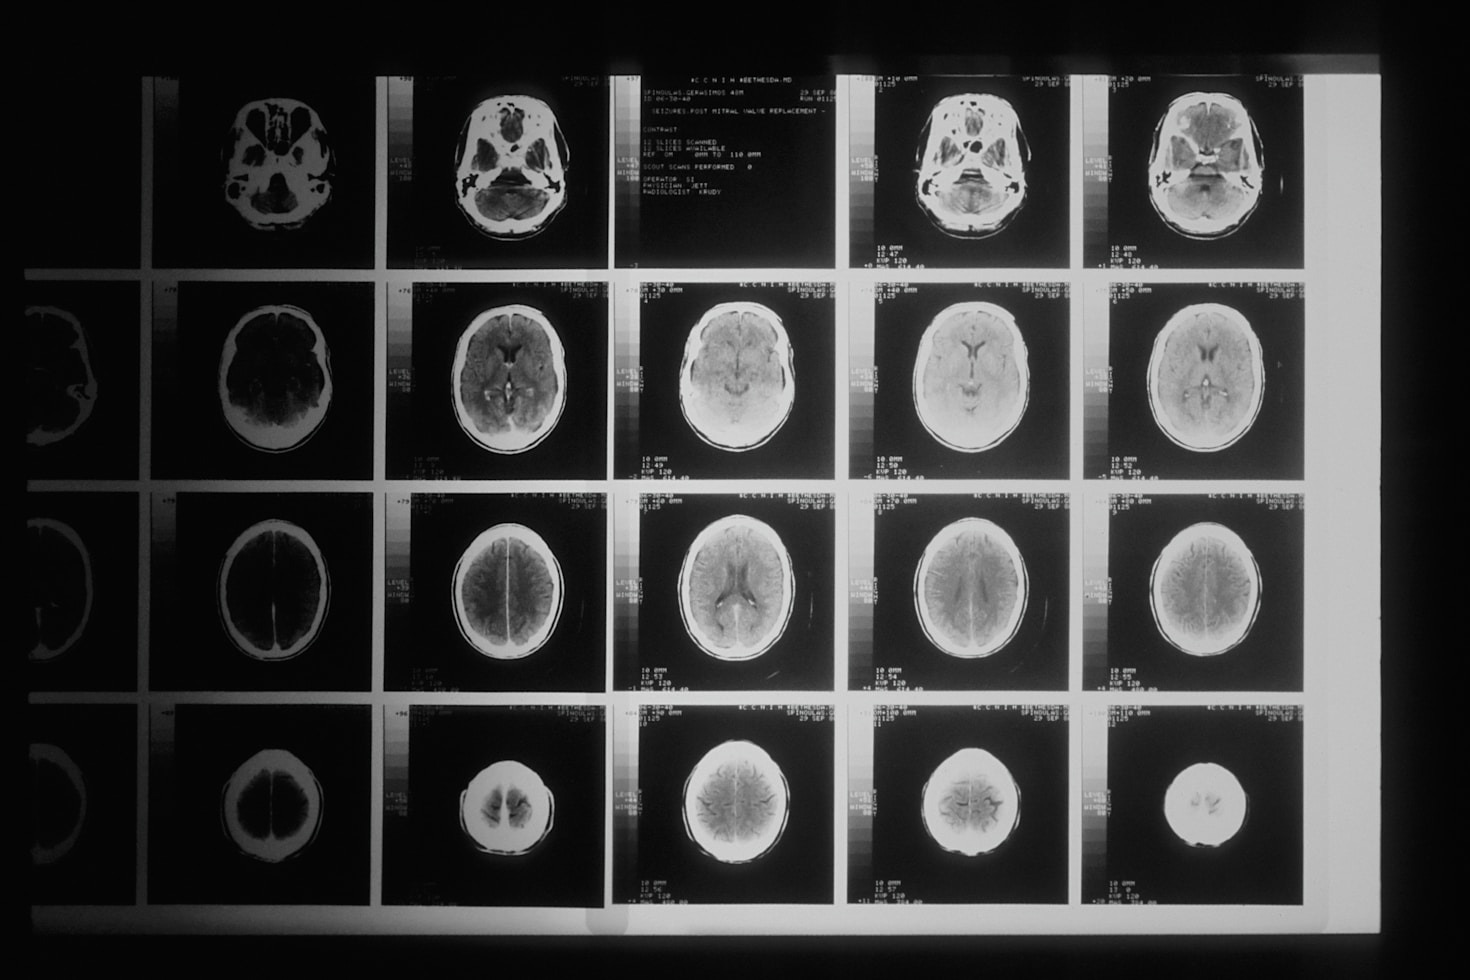

Conheça os principais métodos e exames para o diagnóstico preciso de tumores cerebrais em adultos na prática clínica.